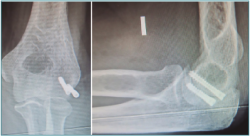

Figura 8. Fractura de la cabeza radial asistida por artroscopia.